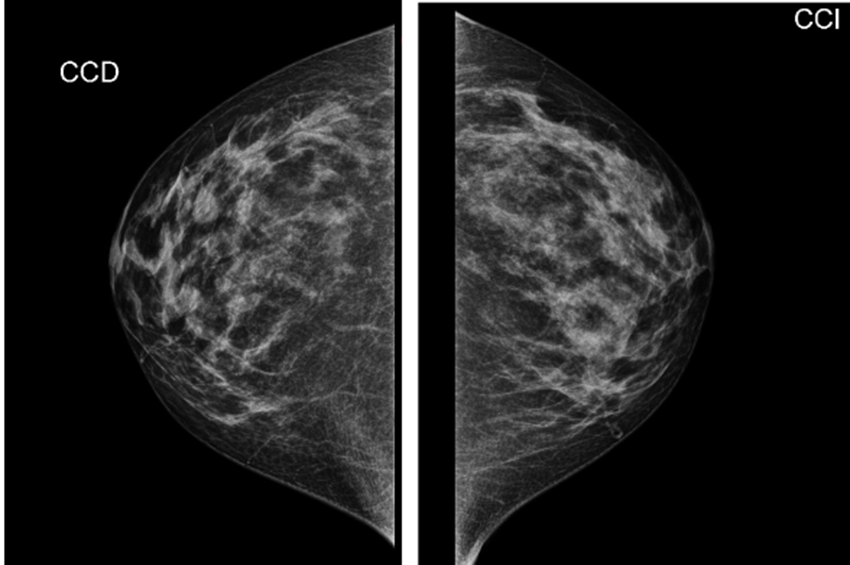

Imágenes Mx

Informe MX:

Hallazgos:

Piel y tejido subcutáneo sin alteraciones.

La unidad areola y pezón normal.

Mamas densas, con distribución heterogénea, observado algunos contornos nodulares, isodensos parciales, bilaterales más evidentes a derecha.

No se reconocen microcalcificaciones agrupadas de manera sospechosa.

Conclusión:

Mamas densas con probable nódulos bilaterales

Se complementará con ultrasonido

Birads 2

ACR C